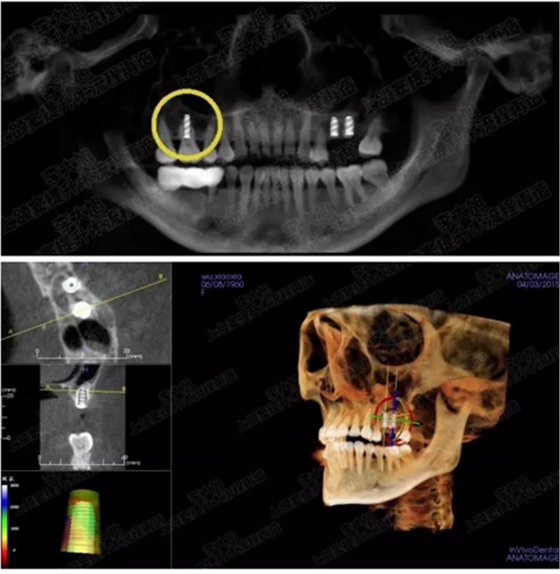

病例一

上頜竇多分隔3mm

05.png

提升8mm

06.png

07.png

修復(fù)時(shí)根尖片

08.png

09.png